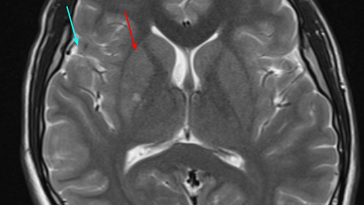

Uncovering the Hidden Connection between IgA Mediated Antiphospholipid Syndrome and Ischemic Stroke